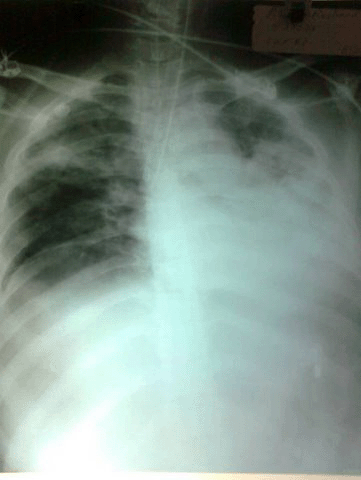

Endobronchial Intubation

01 AUG 2010

Endobronchial Intubation Image- For case details  see the text